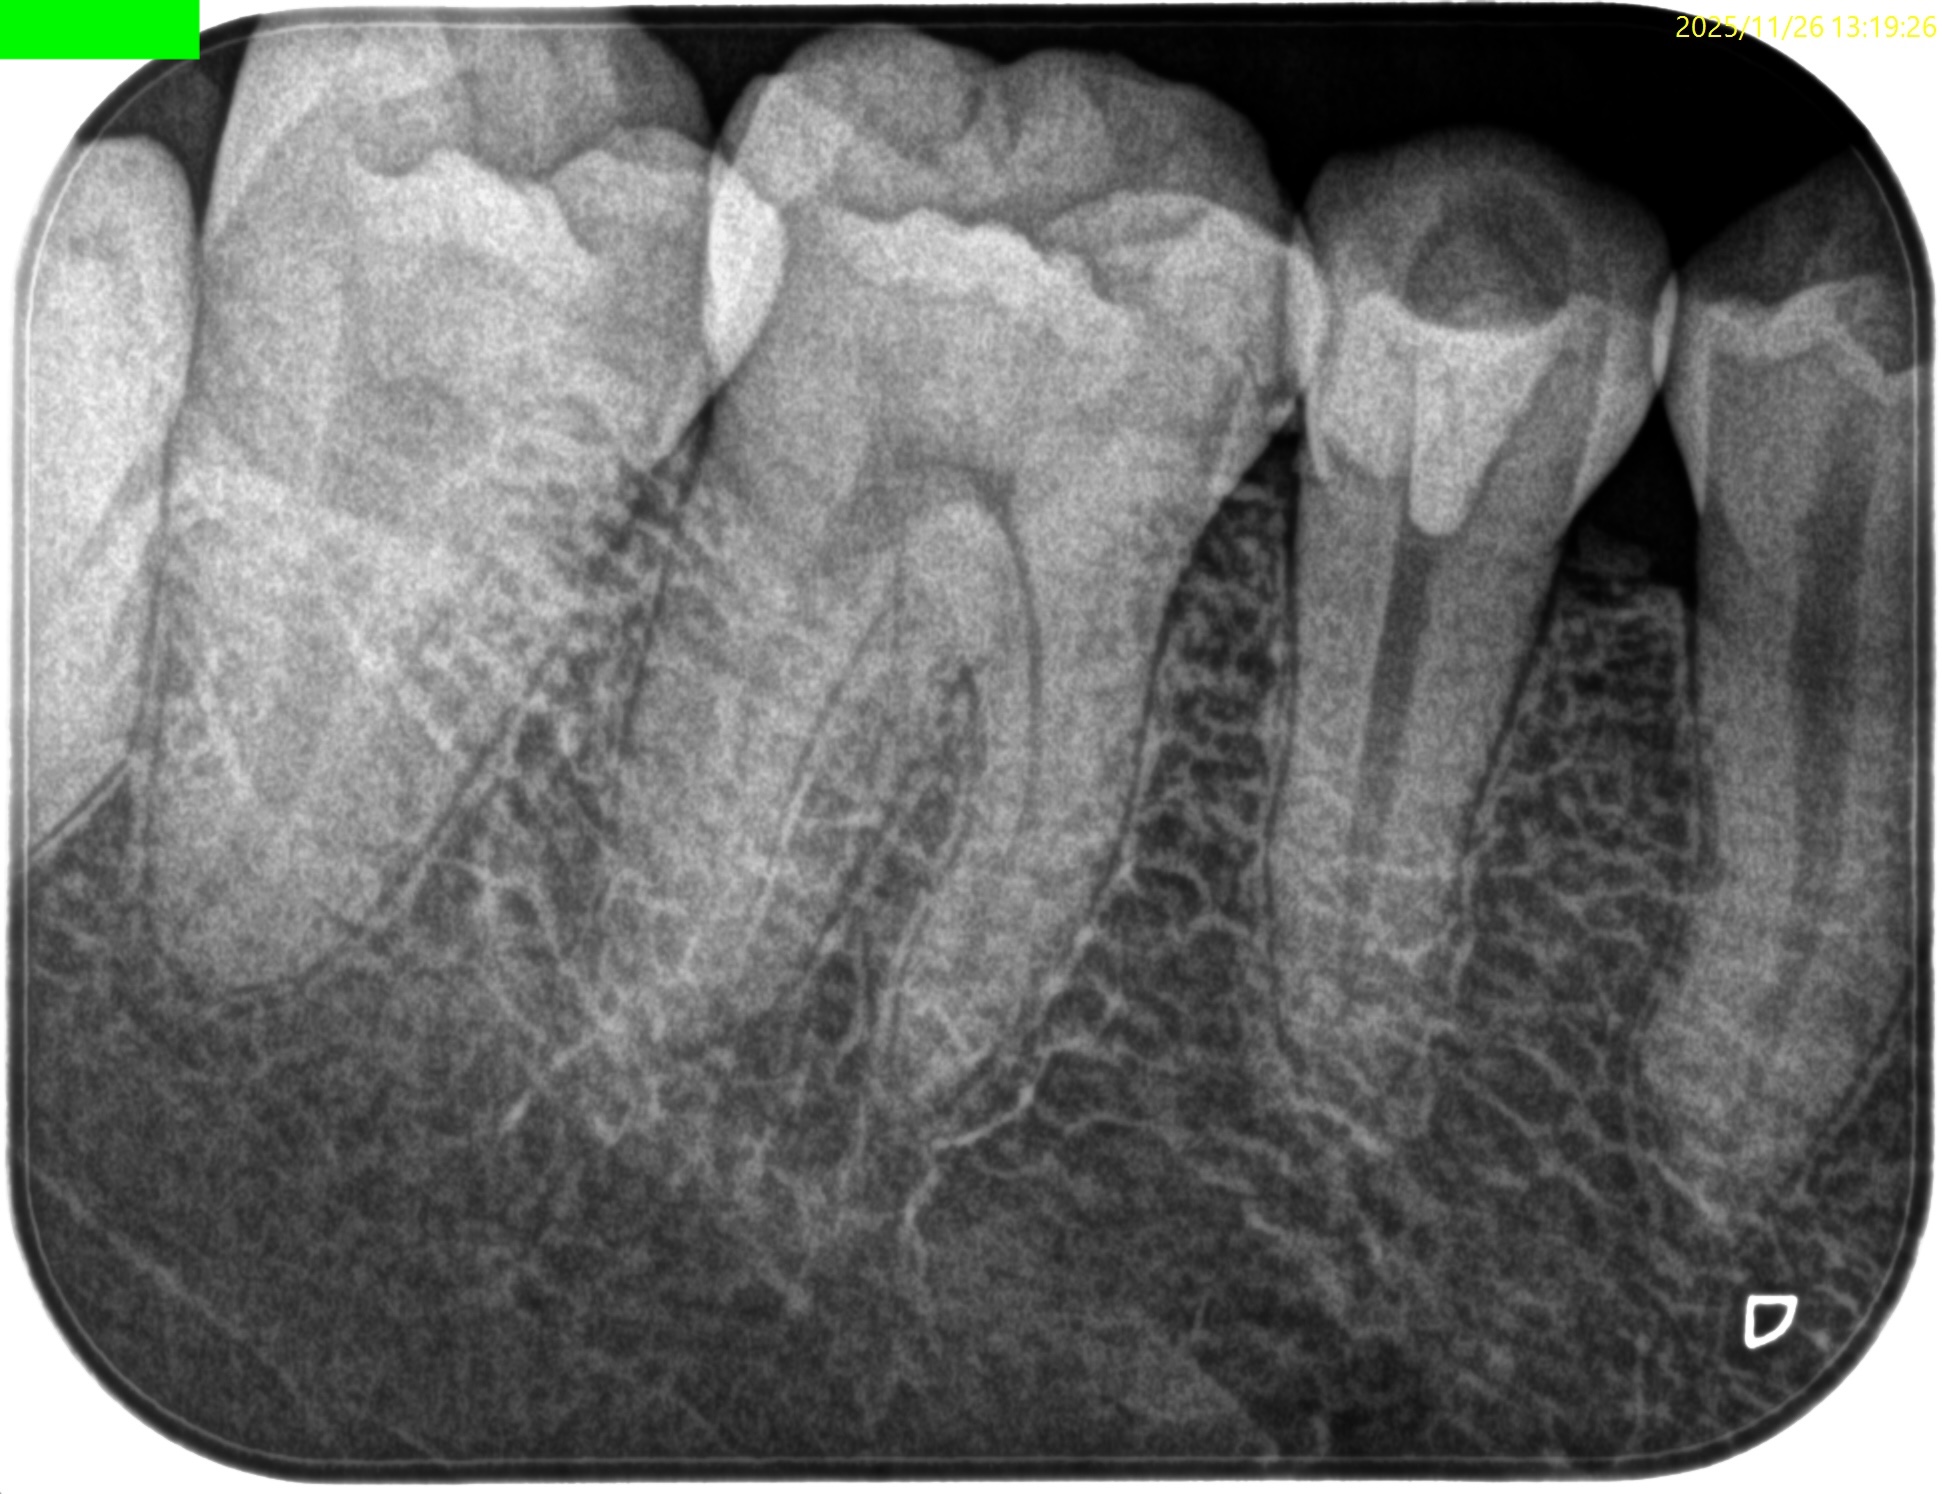

Pre-op Endo test(2025.11.26)

#29に打診痛がある。

紹介元の先生によれば#40.04まで形成したが術後の痛みが続いているという。

根尖病変はない。

根管充填後にPA, CBCTを撮影した。

問題はないだろう。